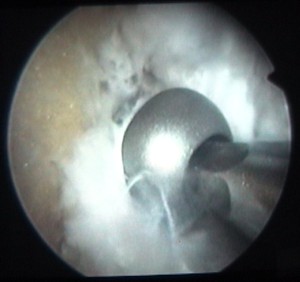

on voit la tête de la vis au milieu de la clé plate |

et le corps de la vis en-dessous |